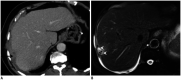

The perihepatic space is frequently involved in a spectrum of diseases, including intrahepatic lesions extending to the liver capsule and disease conditions involving adjacent organs extending to the perihepatic space or spreading thanks to the communication from intraperitoneal or extraperitoneal sites through the hepatic ligaments. Lesions resulting from the dissemination of peritoneal processes may also affect the perihepatic space. Here we discuss how to assess the perihepatic origin of a lesion and describe the magnetic resonance imaging (MRI) features of normal structures and fluids that may be abnormally located in the perihepatic space. We then review and illustrate the MRI findings present in cases of perihepatic infectious, tumor-related, and miscellaneous conditions. Finally, we highlight the value of MRI over computed tomography.